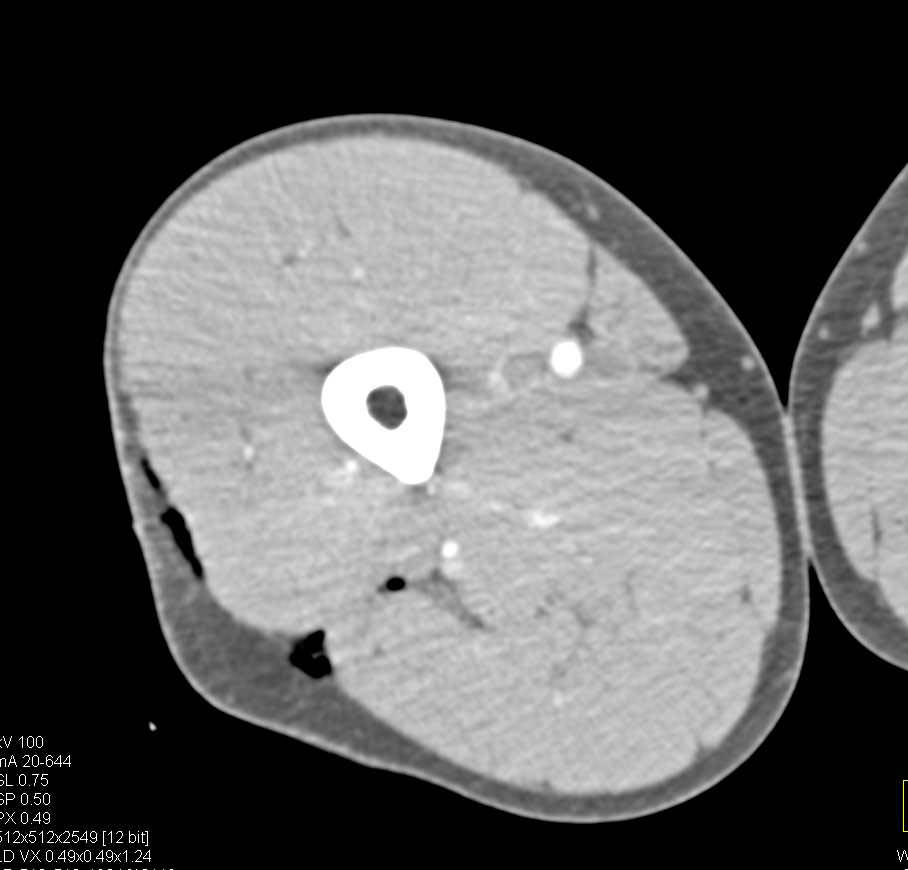

Complex Sacral Fracture with Hematoma and Pelvic Ring Fractures Involving the Symphysis